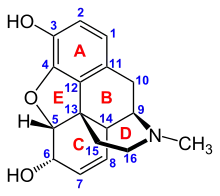

The pharmacodynamic response to an opioid depends upon the receptor to which it binds, its affinity for that receptor, and whether the opioid is an agonist or an antagonist. For example, the supraspinal analgesic properties of the opioid agonist morphine are mediated by activation of the μ1 receptor; respiratory depression and physical dependence by the μ2 receptor; and sedation and spinal analgesia by the κ receptor. Each group of opioid receptors elicits a distinct set of neurological responses, with the receptor subtypes (such as μ1 and μ2 for example) providing even more [measurably] specific responses. Unique to each opioid is its distinct binding affinity to the various classes of opioid receptors (e.g. the μ, κ, and δ opioid receptors are activated at different magnitudes according to the specific receptor binding affinities of the opioid). For example, the opiate alkaloid morphine exhibits high-affinity binding to the μ-opioid receptor, while ketazocine exhibits high affinity to ĸ receptors. It is this combinatorial mechanism that allows for such a wide class of opioids and molecular designs to exist, each with its own unique effect profile. Their individual molecular structure is also responsible for their different duration of action, whereby metabolic breakdown (such as N-dealkylation) is responsible for opioid metabolism.

In the 19th century, two major scientific advances were made that had far-reaching effects. Around 1804, German pharmacist Friedrich Sertürner isolated morphine from opium. He described its crystallization, structure, and pharmacological properties in a well-received paper in 1817.[211][213][208][214] Morphine was the first alkaloid to be isolated from any medicinal plant, the beginning of modern scientific drug discovery.[211][215]

Several semi-synthetic opioids were developed in Germany in the 1910s. The first, oxymorphone, was synthesized from thebaine, an opioid alkaloid in opium poppies, in 1914.[228] Next, Martin Freund and Edmund Speyer developed oxycodone, also from thebaine, at the University of Frankfurt in 1916.[229] In 1920, hydrocodone was prepared by Carl Mannich and Helene Löwenheim, deriving it from codeine. In 1924, hydromorphone was synthesized by adding hydrogen to morphine. Etorphine was synthesized in 1960, from the oripavine in opium poppy straw. Buprenorphine was discovered in 1972.[228]